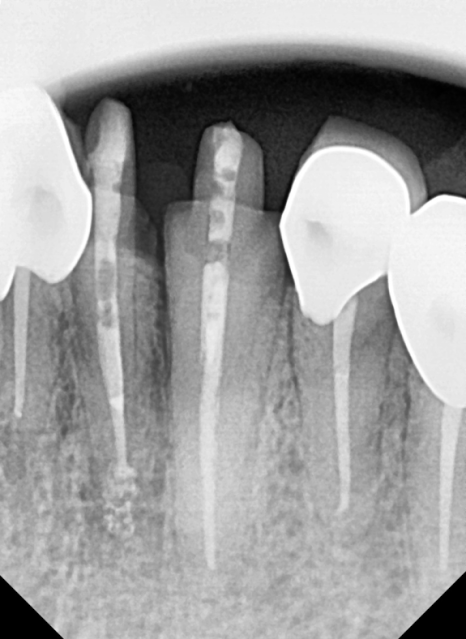

이번에 문제가 생긴 앞니들은

신경치료 후 보철물을 연결하는

스플린트 형태로 제작하기로 계획했습니다.

치료 계획

#12~23 신경치료 및 지르코니아 스플린트

#42, 43, 44 및 #32, 33 신경치료

및 지르코니아 스플린트

3)진행 방식

연세를 고려하여 상악부터 순차적으로 천천히 진행

각 부위당 신경치료를

꼼꼼하게 마무리한 뒤

임시 치아를 거쳐

최종 보철물을 제작했습니다.

240502